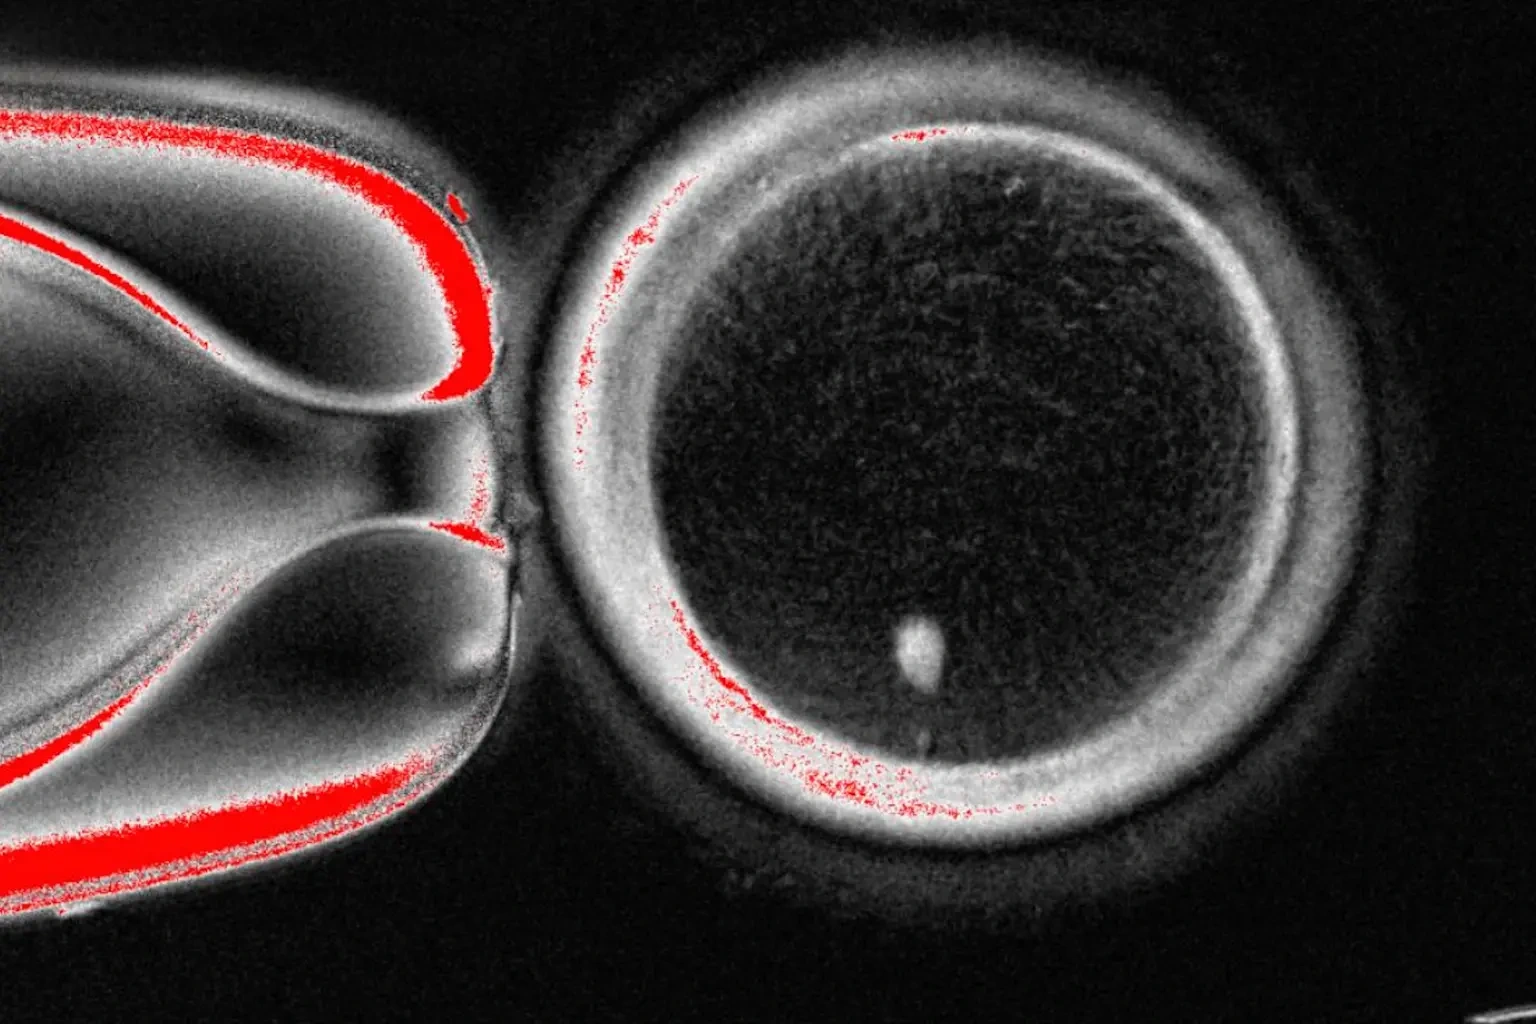

Hình ảnh không ghi ngày tháng này do Phòng thí nghiệm Mitalipov, Trường Đại học Khoa học và Sức khỏe Oregon, Mỹ, cung cấp, cho thấy hình ảnh dưới kính hiển vi của một quả trứng người có chứa nhân lấy từ tế bào da (ảnh: AP).

Nghiên cứu được công bố trên tạp chí Nature Communications đã trình bày chi tiết cách các nhà khoa học Mỹ tạo ra một tế bào trứng người, còn gọi là noãn bào, bằng cách cô lập nhân của một tế bào da và cấy ghép nó vào trứng của người hiến tặng vốn không có nhân.